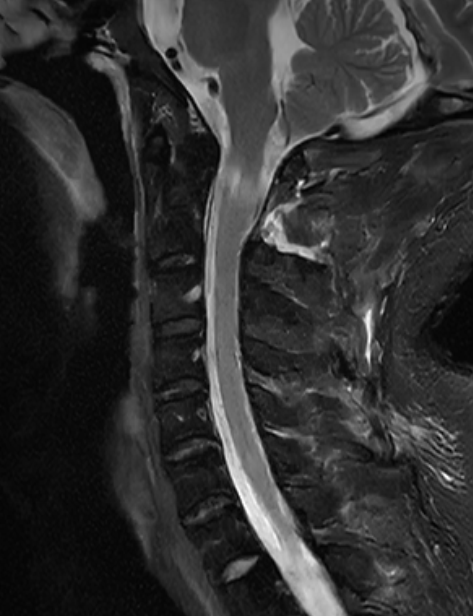

术中增强MRI

为了解决罗先生颈椎上的“定时炸弹”,缓解肢体麻木、行动不便的问题,仇继任及其团队针对罗先生的病情结合术前CT、MRI等影像资料,对治疗方案进行反复讨论和研究,制定了最佳的手术方案——显微镜辅助下精准切除高位颈椎椎管内肿瘤手术。

经过充分的术前准备,仇继任及其团队如期为罗先生进行手术。手术过程中发现肿瘤组织与延髓神经组织粘连紧密,手术难度进一步增大。凭借着精湛而熟练手术技巧及默契的团队配合,仇继任在显微镜下仔细分离肿瘤与脊髓神经组织、精确止血。经过2小时的紧张奋战,手术顺利结束。术后在科室全体医护人员的精心护理下,患者右侧下肢疼痛、麻木症状明显缓解。由于术中未破坏关节突关节,脊柱稳定性得到大部分保留,罗先生术后很快便能起床活动,术后1个星期出院,1个月后随访恢复良好。